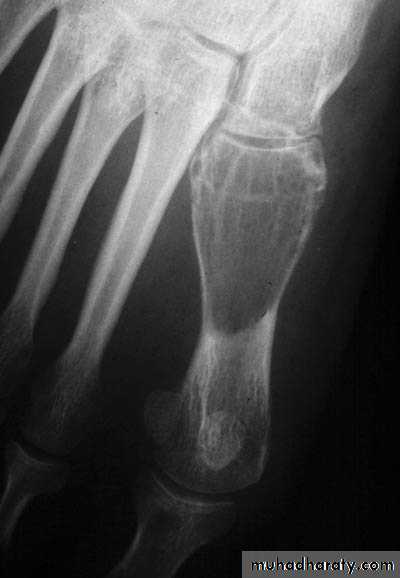

X-ray shows lucent cystic lesion sometimes large and multilocular with bone expansion and cortical thinning it contains multiple calcific spots giving the ground-glass appearance, there is always possible deformity or pathological fracture.

Rarefied area of the bone end reaching just below the articular surface.Eccentric lesion with bone expansion and ballooning with cortical thinning, sometimes pathological fracture.

There may be calcific trabiculations inside the lesion giving it the commonly known saop-bubble appearance.